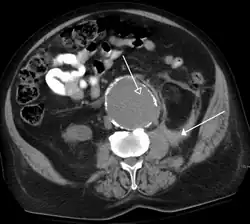

- Tomografia Computadorizada

A Tomografia Computadorizada (TC), também conhecida como uma tomografia computadorizada, é um método de imagem médica que combina várias projeções de raios-X tomadas de ângulos diferentes para produzir imagens detalhadas de áreas transversais de áreas dentro do corpo. As imagens de CT permitem que os médicos obtenham visões tridimensionais muito precisas de certas partes do corpo, como tecidos moles, pelve, vasos sanguíneos, pulmões, cérebro, coração, abdômen e ossos. A TC também é frequentemente o método preferido para diagnosticar muitos cancros, tais como cancro do fígado, do pulmão e do pâncreas.

A TC é frequentemente utilizada para avaliar:

- Presença, tamanho e localização dos tumores

- Órgãos na pelve, tórax e abdômen

- Saúde do cólon (CT colongraphy)

- Estado vascular / fluxo sanguíneo

- Embolia pulmonar (angiografia por TC)

- Aneurisma da aorta abdominal (angiografia por TC)

- Lesões ósseas

- Tecido cardíaco

- Lesões traumáticas

- Doença cardiovascular

- Tomografia computadorizada

O CT scanner produz imagens detalhadas do corpo em 3D. Devido à sua alta resolução, estas imagens podem fornecer informações adicionais em comparação com a radiografia convencional.